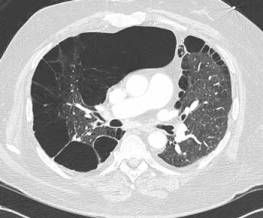

The physical exam showed bilateral diffuse wheezing and crackles. An earlier chest radiograph showed mild hilar prominence. A repeated radiograph showed new bilateral diffuse interstitial infiltrates involving both lungs and bilateral hilar lymphadenopathy. This chest CT scan showed similar findings with a tree-in-bud appearance predominantly in the midlung zones and perihilar areas. Pulmonary function testing results showed a progression from moderate to severe obstructive lung disease and worsening diffusing capacity of the lung for carbon monoxide.

Positive findings of sarcoidosis involving the skin along with bilateral diffuse interstitial lung infiltrates and hilar lymphadenopathy supported a diagnosis of pulmonary sarcoidosis.

Sarcoidosis affects the lungs in 90% of cases. It usually involves the intrathoracic lymph nodes and, less frequently, the lung parenchyma. Up to 50% of patients have symptoms similar to those of asthma, such as cough, wheezing, dyspnea, chest pain, chest tightness, and fatigue.